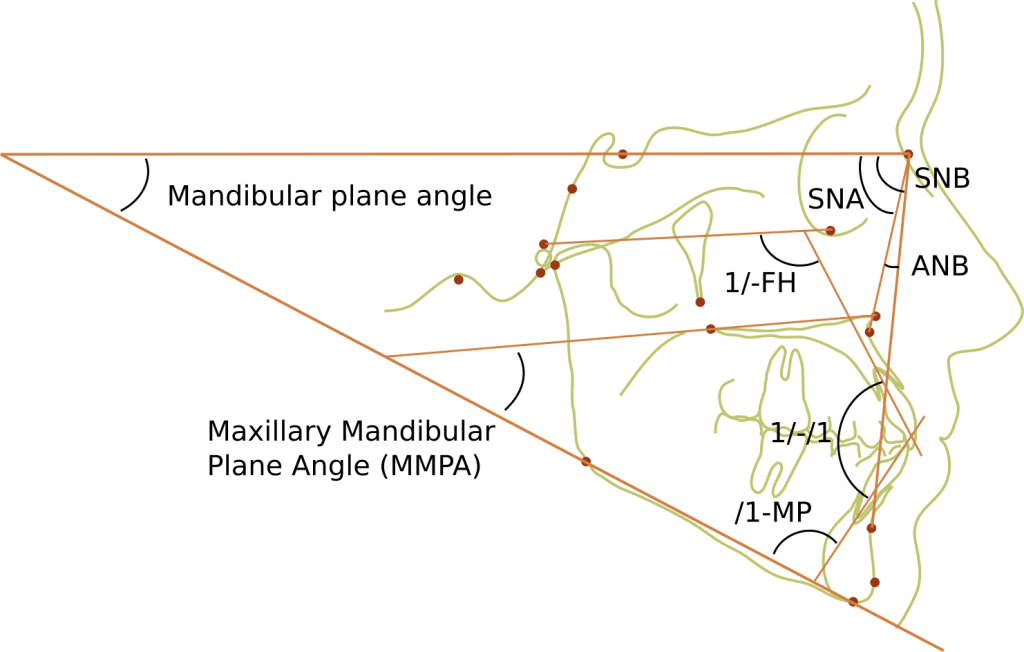

Angular measurements

The angle measurements are established by using 3 landmarks. For example, SNA is taken by drawing a line from Sella (S), to Nasion (N), to Point A (subspinale), and measuring the angle. Significant variation exists between different races. There are many angular measurements used in orthodontics, but these are likely the ones you need to understand (including what values are normal and what variation will mean clinically).

- SNA – normal 82° ± 2. >84° indicates a prognathic maxilla. <80° indicates a retrognathic maxilla.

- SNB – normal 80° ± 2. > 82° indicates a prognathic mandible. <78° indicates a retrognathic mandible.

- ANB – normal 2° ± 2. This would suggest Class I skeletal relationship. >4° could mean either a retrognathic mandible or prognathic maxilla, and suggests a Class II malocclusion. <0° could either mean a retrognathic maxilla or prognathic mandible, and suggests a Class III malocclusion.

- Mandibular plane angle – Gonion to menton is the mandibular plane. It can be visualized externally by placing a straight object on the inferior border of the mandible. When compared to S-N (MP-SN), it gives you the mandibular plane angle. Normal is 14°. >14° suggests a vertical growth pattern with a long lower face and a tendency to Class II. <14° suggests a flat growth pattern with a short face and a tendency towards Class III.

- Maxillary Mandibular Plane Angle (MMPA) – the angle between the mandibular plane and the maxillary plane (ANS to PNS line). Normal value 27° ± 4. The greater the MMPA, the longer the anterior facial height and tendency to Class II. The smaller the MMPA, the shorter the facial height and tendency to Class III.

- Y-axis – S-N to S-Gn: a larger angle indicates more vertical development, long face and anterior open bite tendency.

- 1/-FH – Upper incisor angulation in relation to the Frankfort horizontal plane, usually 60°. A smaller angle indicates flared incisors.

- /1-MP – Lower incisor angulation in relation to the cranial base, usually 90-100°. A large angle indicates flared incisors.

- 1/-/1 – Interincisal angle, average value 130°.